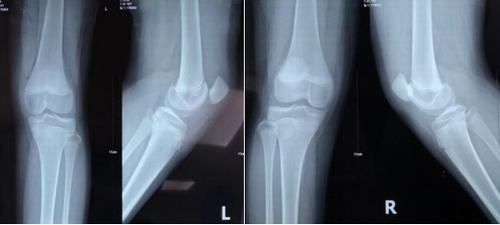

X線片示:髕骨脫位